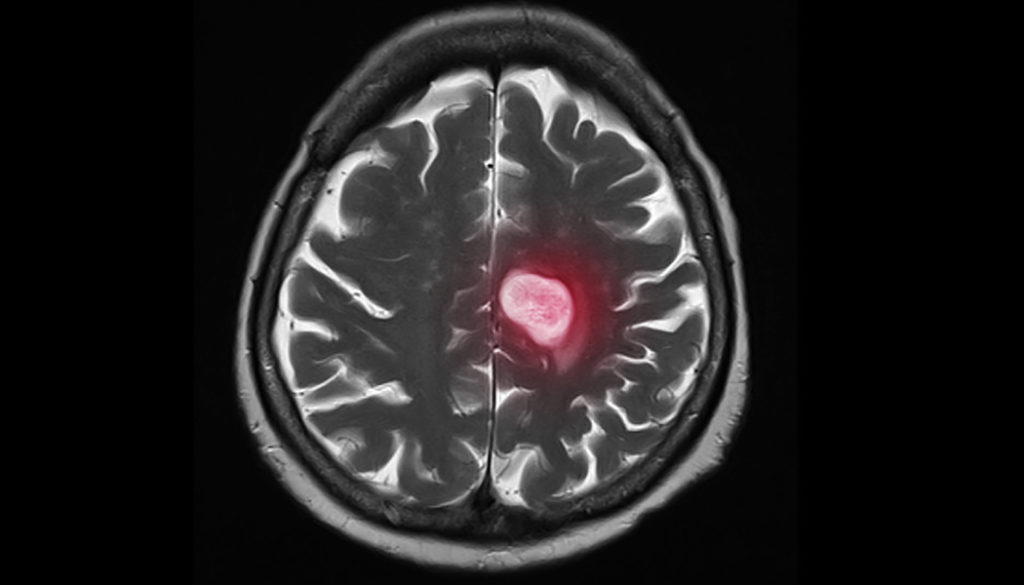

Cancer can spread to any part of the body, but the most common sites of metastasis are the bones, brain, liver and lungs. Although metastasis causes more than 90% of cancer-related deaths, it only receives less than 5% of research funding.

National Foundation for Cancer Research funded researcher Dr. Daniel A Haber recently unearthed an exciting discovery that may add years to the lives of late-stage breast cancer patients. Dr. Haber is fascinated by understanding drug resistance on a deeper level by studying individual tumor cells in patients’ blood. In December 2020, Dr. Haber and his team shared their exciting findings on how brain metastasis, or the spread of cancer to the brain, may be prevented. Brain metastases occur in about 10% of all patients with cancer and in as many as a third of women with advanced metastatic breast cancer. Though experts have made great strides in suppressing the spread of cancer, there is still little known about the cellular pathways that enable cancer cells to selectively grow in the brain; that is, until Dr. Haber and his research team identified a signaling pathway which appeared significantly more active in brain metastases from breast cancer. “We were looking for what properties of some breast cancer cells made it possible for the cells to grow in the brain, which is a rare but often deadly complication of breast cancer,” Dr. Haber explained. “We weren’t sure what we would find. In a way that’s what makes the discovery process so exciting.” The research commenced approximately 10 years ago while investigating circulating tumor cells (CTCs). As their research progressed, the team homed in on a specific signaling pathway named HIF1A. Using cells from women with breast cancer, the team observed how these cells acted in animal models. It was discovered that if HIF1A was suppressed, the rate of proliferation (or rapid growth) was reduced. Simply put, blocking the HIF1A signaling pathway could reduce the rate of brain metastasis or even prevent it all together. “HIF1A is not specific to brain metastasis, since it’s a very broadly activated pathway in many cancers,” Dr. Haber began. “However, it appears to be more active in brain metastases from breast cancer than in primary breast cancers, and that may help explain what makes these metastases to the brain so unique and so difficult to treat.” The pathway identified in this research is already well known in the cancer world, however its special relevance to the brain was not known until now. Theoretically, a drug could be developed to suppress HIF1A and, in turn, prevent the spread of cancer. While a very promising discovery, Dr. Haber explains that there is far more work to be done. “There are a few HIF1A suppressing drugs now being tested in clinical trials for other indications,” Dr. Haber said, “However, we would have to expand this to multiple different models and systems before we could contemplate an intervention.” In regard to the length of time it takes to have a discovery such as this transitioned to mainstream treatment, Dr. Haber explains that it “depends on the discovery, its potential applications and some ‘luck’.” While the process from discovery to clinical treatment is getting faster all the time, it is likely going to take five to ten years before this finding is implemented into treatment. As for Dr. Haber, he has already planned plenty of work […]

It is the one word you do not want to hear in a cancer diagnosis: metastasis. It represents the figurative death-knell; once a cancer has spread to other parts of the body, survival rates plummet and what treatments do exist switch from curative to palliative. The dividing line metastatic cancer (stage IV cancer) can even be seen in funding, where 93 percent of monies go to preventative measures and early detection, rather than for therapies to combat cancer on the move within the body. And yet, in understanding the mechanisms of metastasis, the cure for this stage of cancer may be found. It is the reason investigators are taking a fresh look at exactly what happens when cancerous cells first break away from their host tumor. Not surprisingly, metastasis is a complex biological process; it is actually an amalgam of several different events. Douglas Hurst, Ph.D., assistant professor in the UAB Department of Pathology, and Danny Welch, Ph.D., associate director of Education at the KUCC and NFCR funded scientist, conducted a literature review of more than 10,000 publications on metastasis, and found that in order for a cancerous cell to be “metastatic,” a cell has to exhibit the following qualities: Motility and Invasion By definition, metastatic cells must be able to migrate from the original tumor. Invasion, the defining feature of malignancy, is the capacity for tumor cells to disrupt the basement membrane (a thin, fibrous, extracellular matrix of tissue that separates the lining of an internal or external body surface from underlying connective tissue) and penetrate underlying stroma (the tumor’s support structure.). Motility alone is not sufficient; if a cell successfully breaks away from a tumor but subsequently dies, it is not considered metastatic. Ability to Modulate the Secondary Site Metastatic cancer’s ability to co-opt local tissue is a wonder of biology. In one fell swoop, cancer recruits new cells into the local microenvironment, elicits mobilization of immune/inflammatory cells, restructures other tissues, alters metabolism of surrounding stroma, cancels any antitumor actions by the immune system, manipulates the behavior of other cancer cells, alters the extracellular matrix, and restructures normal behaviors of other cells. Plasticity Primary or secondary, tumors are not static; on a cellular level they are, in fact, very dynamic. Cancer cells must adapt their metabolism to meet the demands that accompany rapid growth of the primary tumor and colonization of distinct metastatic sites. Moreover, neoplastic cells can alter growth rates of other cells, drug resistance, and metastatic capability. Ability to Colonize Secondary Tissues Colonization of secondary tissues is the standout feature of metastatic cancer. In the Hurst-Welch study, it is suggested that if a tumor cell or cells breaks away from the primary tumor and survives, but cannot take root elsewhere in the body, metastasis is not taking place. Once metastasis occurs, survival rates can plummet as much as 90 percent, so it is critical to discern the events of the entire metastatic cascade. Recent research shows promise: Welch, an NFCR-funded fellow, and his team have discovered eight of the 35 known cancer metastasis suppressor genes. Further study based on these discoveries may lead to the design […]